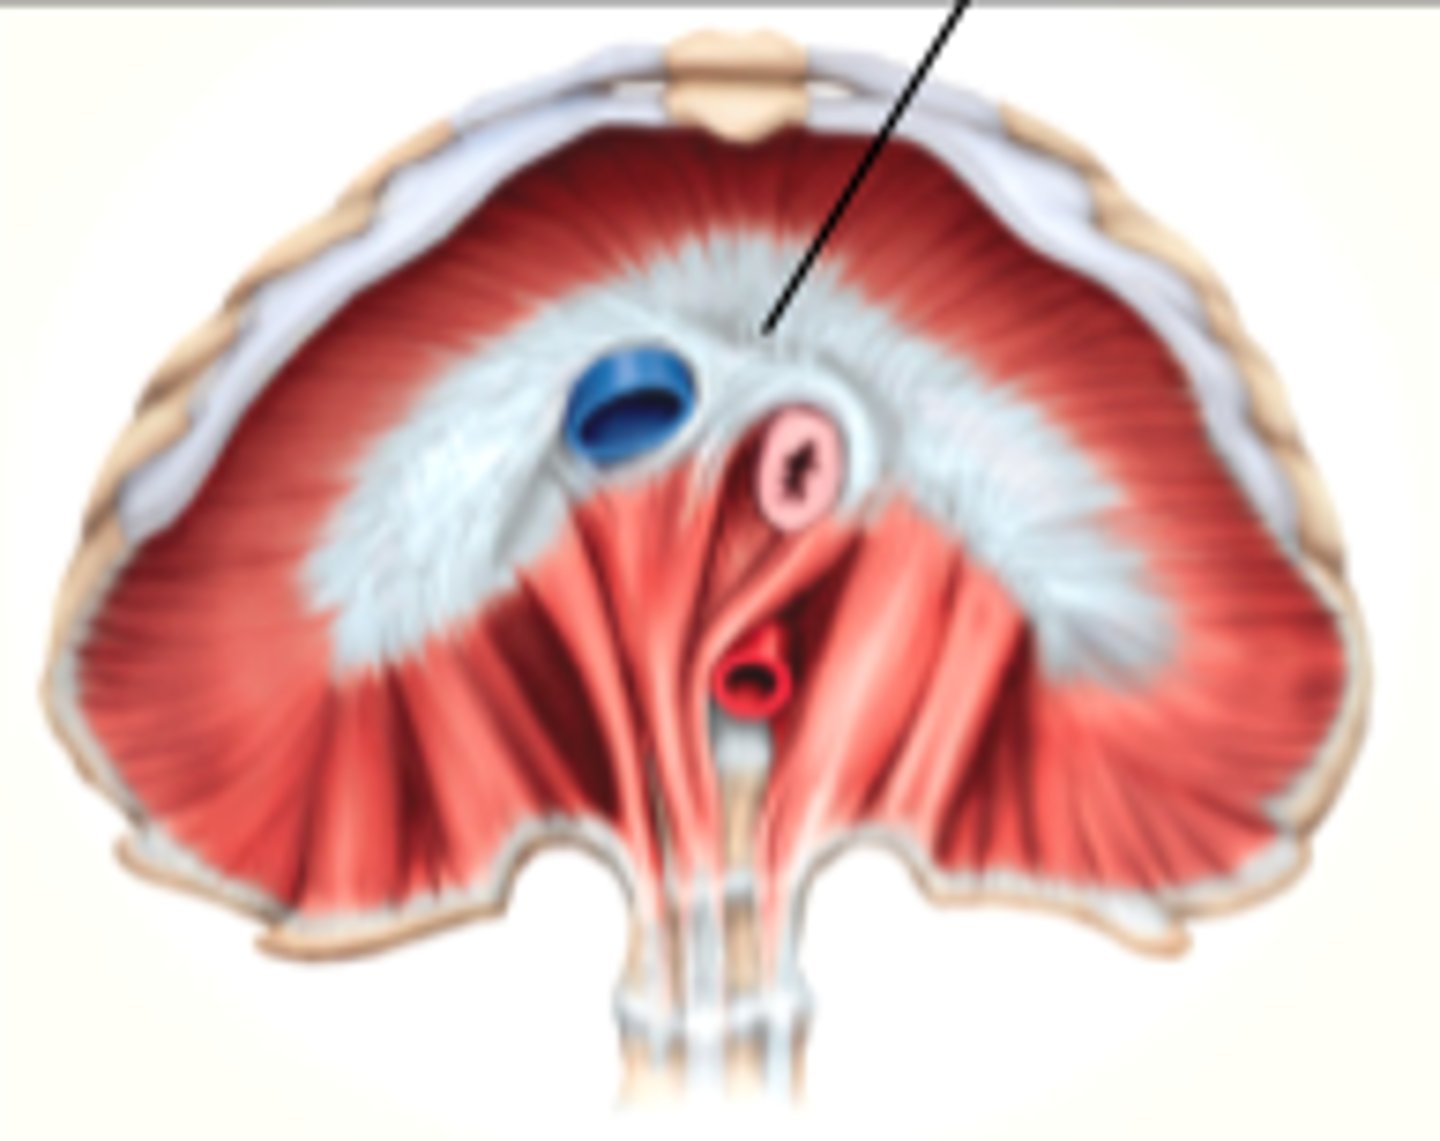

central tendon of the diaphragm

costodiaphragmatic recess

phrenic nerves

pericardiophrenic arteries (and veins)